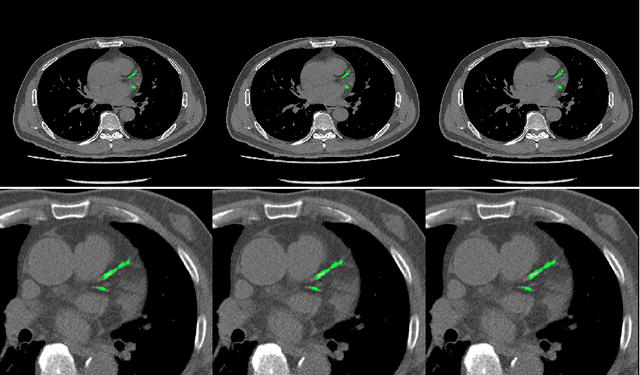

Abstract:Cardiovascular disease (CVD) is a common and strong threat to human beings, featuring high prevalence, disability and mortality. The amount of coronary artery calcification (CAC) is an effective factor for CVD risk evaluation. Conventionally, CAC is quantified using ECG-synchronized cardiac CT but rarely from general chest CT scans. However, compared with ECG-synchronized cardiac CT, chest CT is more prevalent and economical in clinical practice. To address this, we propose an automatic method based on Dense U-Net to segment coronary calcium pixels on both types of CT scans. Our contribution is two-fold. First, we propose a novel network called DenseRAUnet, which takes advantage of Dense U-net, ResNet and atrous convolutions. We prove the robustness and generalizability of our model by training it exclusively on chest CT while test on both types of CT scans. Second, we design a loss function combining bootstrap with IoU function to balance foreground and background classes. DenseRAUnet is trained in a 2.5D fashion and tested on a private dataset consisting of 144 scans. Results show an F1-score of 0.75, with 0.83 accuracy of predicting cardiovascular disease risk.